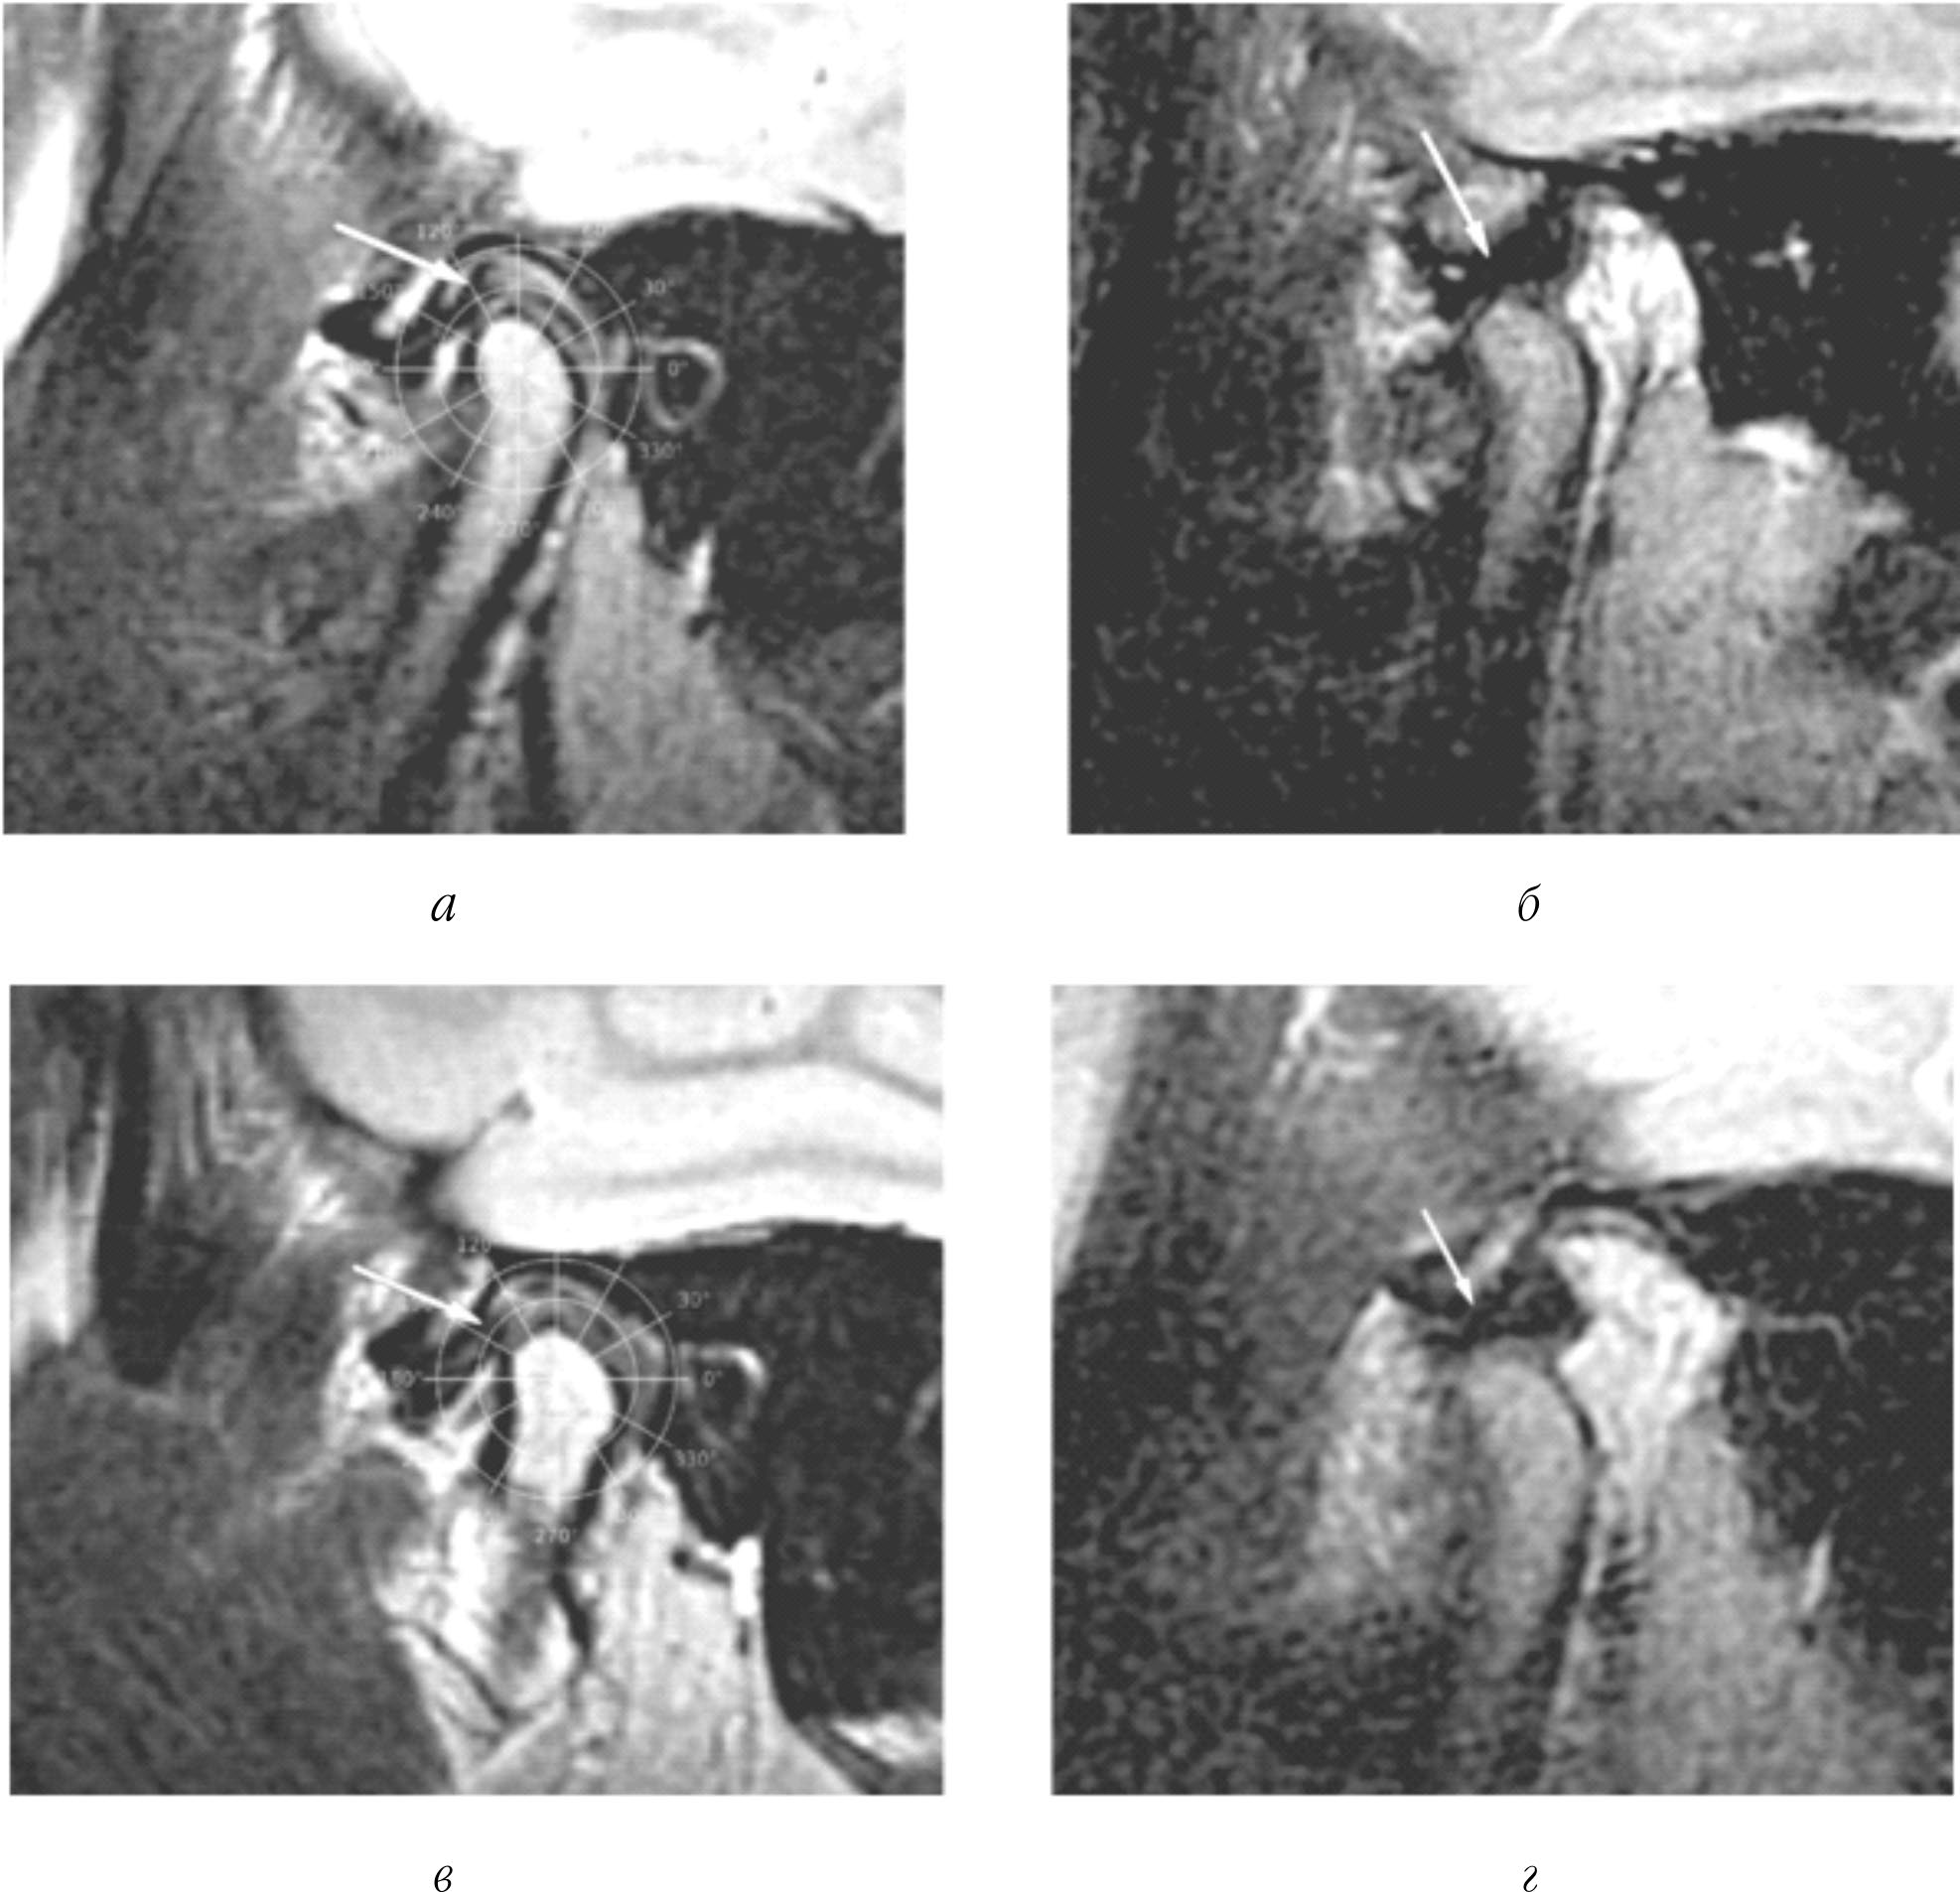

После клинического осмотра проведена магнитно-резонансная томография височно-нижнечелюстного сустава с правой и левой стороны в положении множественного фиссурно-бугоркового контакта зубов и с широко открытым ртом. Сагиттальные срезы с правой стороны в положении множественного фиссурно-бугоркового контакта зубов и с широко открытым ртом представлены на рис. 4, а, б, соответственно.

Сагиттальные срезы с левой стороны в положении множественного фиссурно-бугоркового контакта зубов и с широко открытым ртом представлены на рис. 4, в, г, соответственно.

При оценке магнитно-резонансной томографии пациента определены асимметричные изменения состояния внутрисуставных структур с правой и левой стороны:

суставные диски справа и слева не деформированы, справа дислокация отсутствует (задний полюс суставного диска на 90° ± 15°), диск полностью вправляется, слева диск полностью дислоцирован (задний полюс суставного диска на 180° ± 15°), вправление отсутствует.

То есть в соответствии с комплексным критерием: справа: обратимая дислокация (90° ± 15°, недеформированный, полное), слева: необратимая дислокация (180° ± 15°, недеформированный, отсутствует).

Это говорит об асимметричном разрушении внутрисуставных структур: наличии необратимой дислокации левого суставного диска.

Рис. 4. Пациентка 2. Магнитно-резонансная томография височно-нижнечелюстного сустава справа (а – в положении центральной окклюзии; б – с широко открытым ртом) и слева (в – в положении центральной окклюзии; г – с широко открытым ртом)

После обследования поставлен диагноз: К 07.6 – дисфункция височно-нижнечелюстного сустава, обратимая дислокация суставного диска справа и необратимая дислокация слева. При планировании ортодонтического лечения рекомендовано создать условия для сохранения положения суставного мыщелка и репозиции диска справа и улучшения положения суставного мыщелка без репозиции диска слева, создав для этого защитную окклюзионную поддержку.